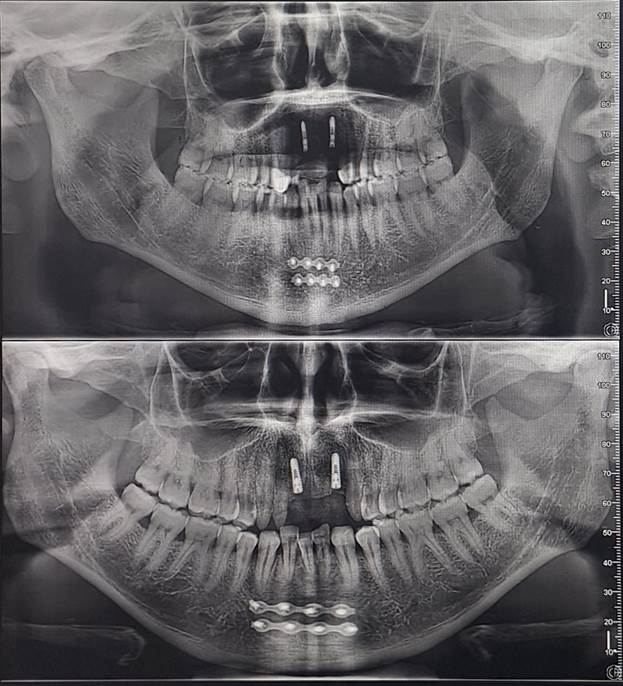

I recently received images of the damage when I got my teeth

repaired and have provided them below.

I went to the mirror and saw the extent of the damage. My lower jaw had split

into two halves, divided straight down the front center. I decided not to

Initially,

I believed the damage had been repaired correctly. But over time, the injury

had pulled closer together, pushing the bottom middle tooth out of alignment. I

realized I would need to go to the hospital to have it broken and reset. The

thought of enduring that pain again was daunting. However, when I visited

DentaFly, they reassured me that the healing had gone well, and the misaligned

tooth was perfectly fine and fixable. So, I requested a quote for the necessary

treatment.